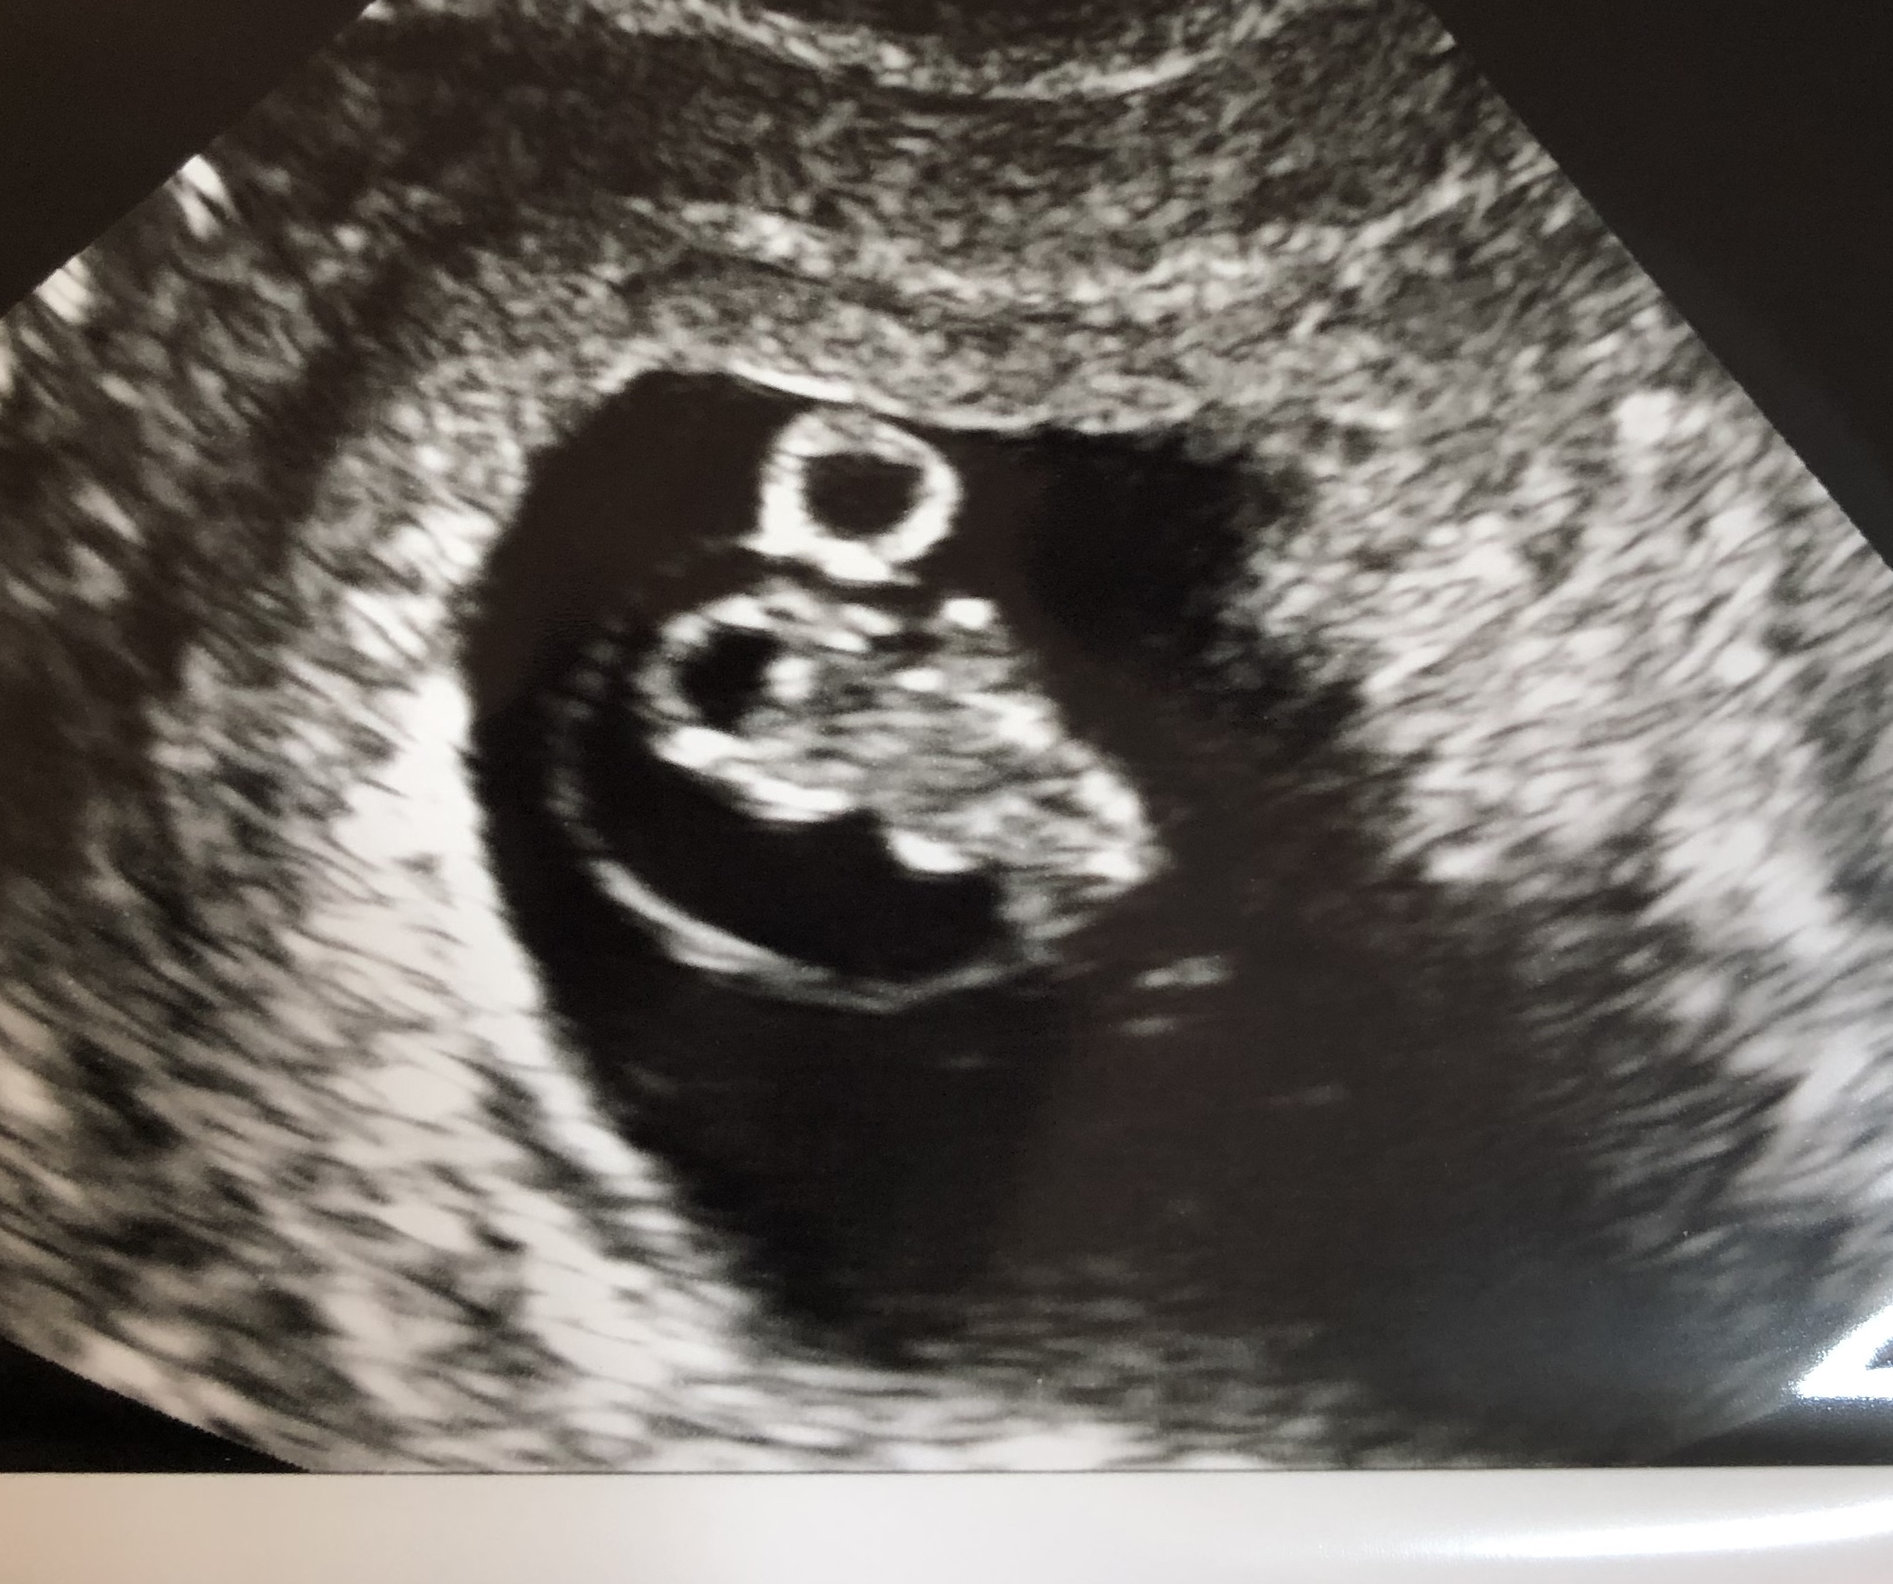

6 weeks, 4 days, and we saw his/her heartbeat!!!! 116 bpm, which doc said is on the slow side, but normal for having a brand new heart. Already in love, and praying we welcome this baby in February